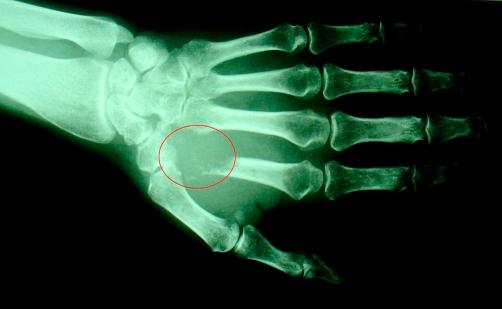

We report a 51-year-old Iranian woman who presented with back pain and paraparesis. MR imaging study of her spine showed an enhancing cystic lesion at the level of conus medullaris. Despite detailed investigation, no specific aetiology was found till a bone scan obtained to evaluate an agonizing pain on the dorsum of the left hand revealed photon deficient area within the left kidney in addition to oseoblastic bony lesions. After thorough imaging investigation she underwent radical nephrectomy which confirmed renal cell carcinoma.

我们报告一名51岁的伊朗女性,她出现背痛和双下肢轻瘫。其脊柱的磁共振成像研究显示圆锥水平有一个强化的囊性病变。尽管进行了详细检查,但直到为评估左手背部的剧痛而进行骨扫描时,除了成骨骨性病变外,还发现左肾内有光子缺乏区,才发现具体病因。经过全面的影像学检查后,她接受了根治性肾切除术,病理证实为肾细胞癌。